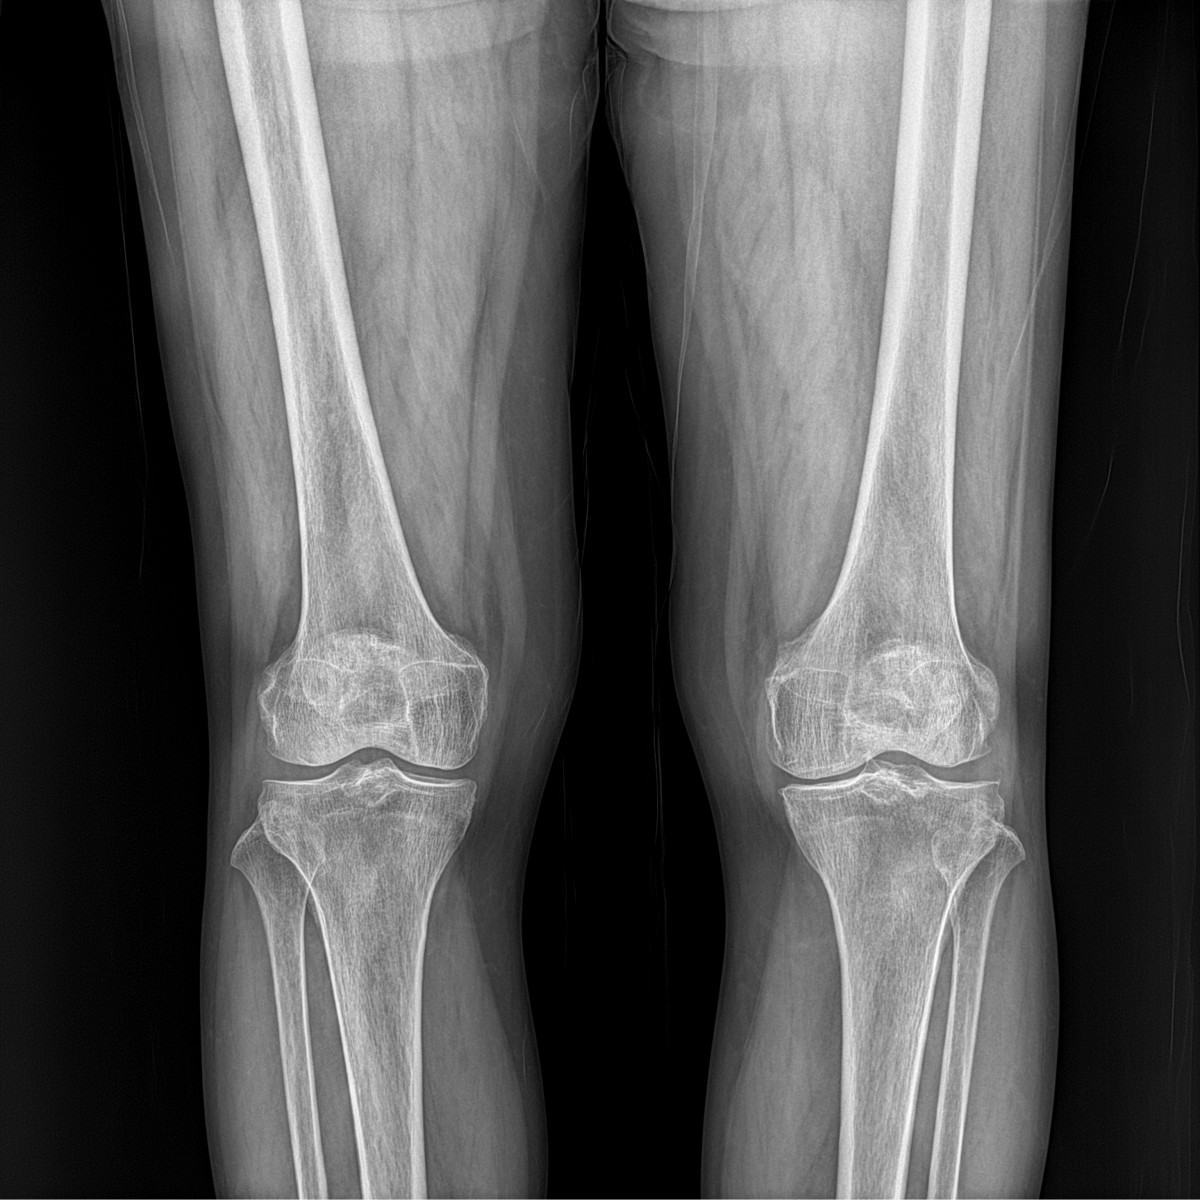

이재상원장님 무릎 인공관절 치환술 이석O 환자

작성자 최고관리자 댓글 0건 조회 702회 작성일 25-09-16 17:12

dae765e4d9ac96aee867c9d6292d8784_1758010355_0663.jpg